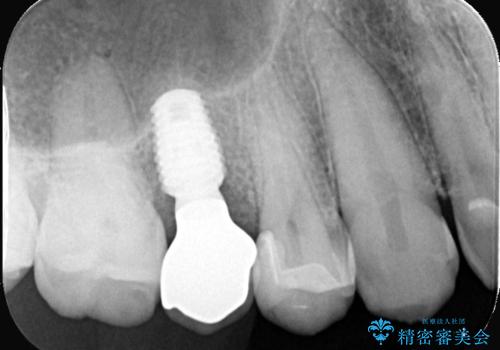

右上5番が根尖性歯周炎と歯周病が同時に併発しており、骨が大きく溶け、歯の動揺も著しかったため保存困難と判断をし抜歯してインプラントで治療を行いました。

インプラントはインプラント周囲炎になりにくいスクリュータイプを使用しています。

従来のインプラント治療では、オペを二回に分けることが主流でしたが今は1回のオペで治療を終える事が出来るようになりました。

インプラントと骨が強度にくっつくように骨密度を上げながらドリリングを行っているのと、患者様の骨の状態に合わせてインプラントの形態を選ぶことで可能となっています。

オペの回数を最小にする事で患者様の治療への負担が減り、治療期間も従来の治療より大幅に短くする事が可能です。